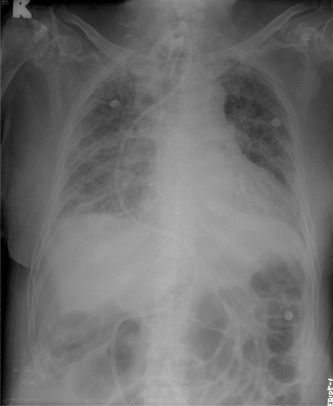

A 71-year-old woman with a history of squamous cell carcinoma of the esophagus (cT3N0M0, stage IIA) had received an esophagectomy with esophageal reconstruction 1 year previously. This patient received nutritional support via a duodenostomy. She was admitted to hospital with aspiration pneumonia and was cared for in the intensive care unit due to acute respiratory failure. The gastroenterologists were consulted about the placement of an enteral feeding tube as a result of obstruction of the feeding tube from the duodenostomy route.

We tried to establish a feeding tube through the duodenum and a guide wire was first placed into the jejunum via single-balloon enteroscopy. The transnasal jejunal feeding tube was then pulled out from the oral cavity and a guide wire was used to access the jejunum. We held the guide wire, which passed through the lumen of the feeding tube, and slowly pushed the jejunal tube forward. Finally, we checked the position of the jejunal tube using plain film radiographs of the chest and abdomen. The procedure went smoothly and the feeding tube worked well (Fig. 1 ).

A standard 12-Fr flexible nasoenteral feeding tube is successfully placed into ...

Figure 1.

A standard 12-Fr flexible nasoenteral feeding tube is successfully placed into the jejunum.